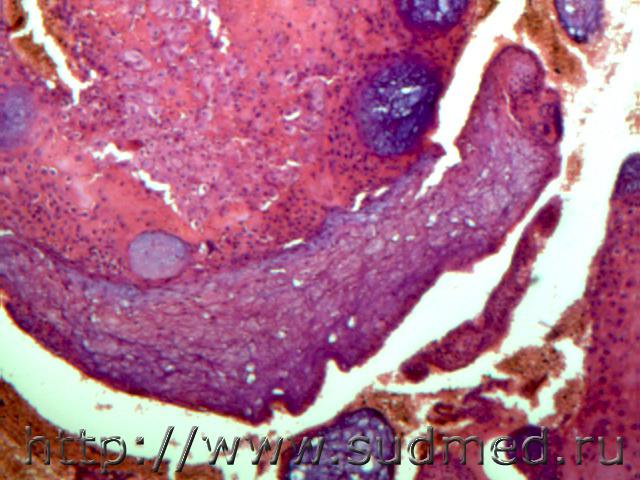

Плоскоклеточный рак шейки матки с ороговением(видны участки тяжелой дисплазии, вторжение в просвет желез, нарушение стратификации и т.д.)